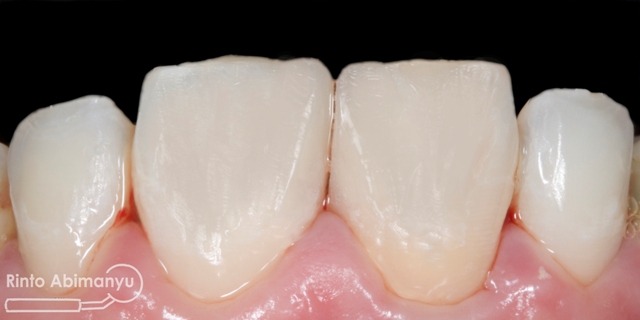

Alhamdulilah ini hasil akhir dari gigi 11 dan 21…

Gigi 11 dan 21 setelah selesai konturing dan pemolesan

Alhamdulillah semua rencana dari mulai perawatan ulang saluran akar sampai memperbaiki tambalan bisa selesai dalam 2 kunjungan dan hasil yang sesuai harapan… Pasien senang dan saya pun lebih senang 😀